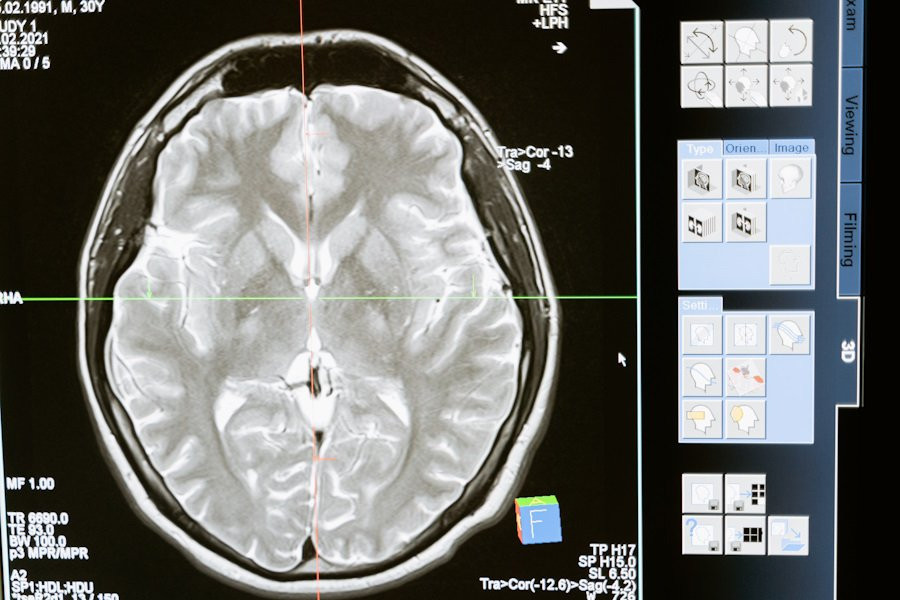

Ученые из Washington University in Saint Louis и University of California обнаружили, что небольшие участки мозга могут находиться в состоянии микродремоты, в то время как остальная часть мозга остается бодрствующей. Открытие, опубликованное на портале Nature Neuroscience, проливает свет на ранее неизвестные свойства сна и бодрствования.

Исследование показало, что наиболее надежные сигнатуры состояний мозга обогащены ритмами от 0,1 до 20 Гц. В рамках работы ученые рассматривали возможность того, что фундаментальная единица состояния мозга может иметь масштаб миллисекунд и микрометров. Используя нейронную активность высокого разрешения, зарегистрированную в десяти областях мозга мыши на протяжении 24 часов, исследователи обнаружили, что состояния мозга надежно идентифицируются благодаря быстрой активности.

Состояния сна и бодрствования можно классифицировать на основе нейронной активности, измеренной в миллисекундах и микрометрах. В отличие от традиционных ритмов, это встраивание сохраняется при частотах выше 1000 Гц и остается устойчивым к различным подсостояниям и волновым ряби. Кроме того, отдельные области мозга периодически переключались между состояниями независимо от остальной части мозга, что совпадало с кратковременными изменениями в поведении.